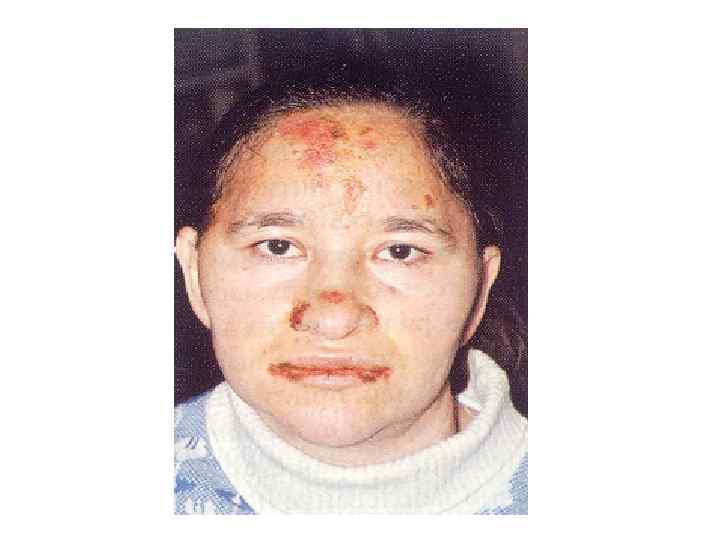

Нередки первичные обращения: • • туберкулез; сифилис; заболевания крови; системная красная волчанка; гиповитаминозы; сахарный диабет; проявления профессиональных заболеваний.

Осмотр: Внешний осмотр: Общий вид больного (habitus); Симметрия лица; Цвет кожных покровов лица, конечностей, открытых участков тела; • Состояние волосистой части головы; • Состояние красной каймы губ, конъюнктивы глаз, крыльев носа. • •

Осмотр собственно полости рта Общий осмотр слизистой оболочки: - цвет; - увлажненность; - наличие участков гиперемии; - наличие отека; - наличие элементов поражения (эрозии, язвы, налет и т. д. ); • - состояние выводных протоков слюнных желез. • • •